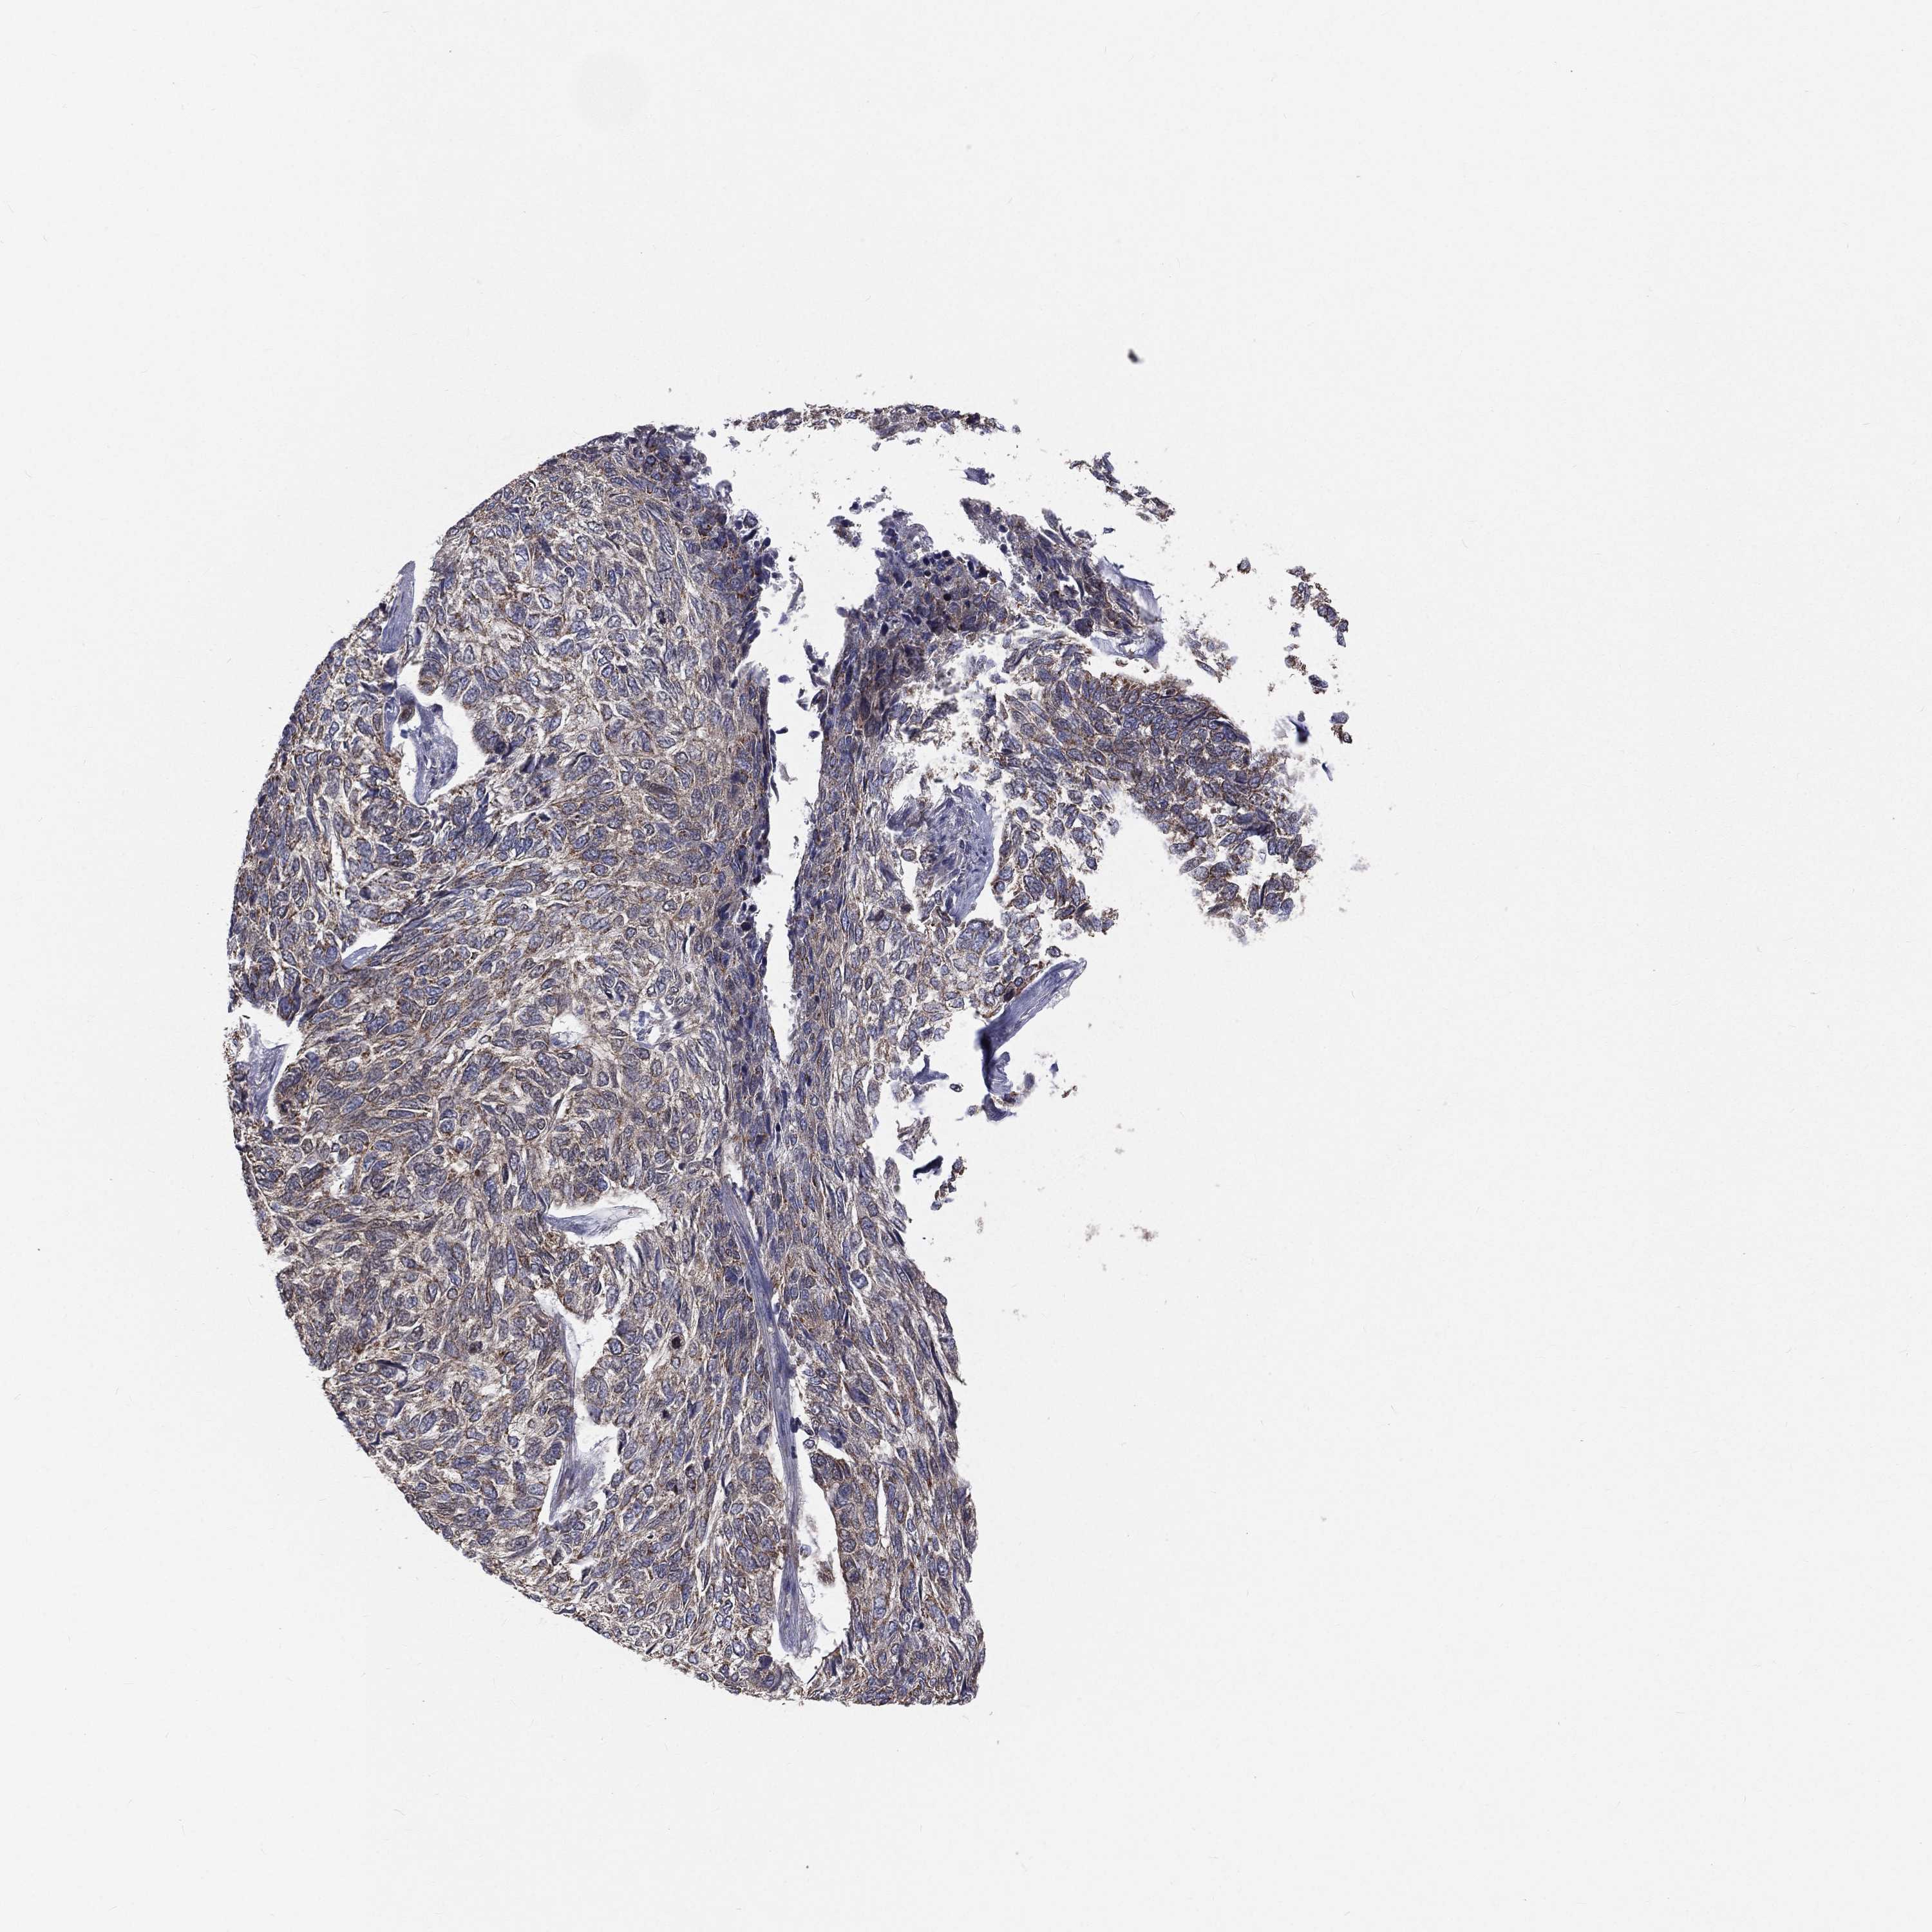

SKIN CANCER - Protein expressioni

A mouse-over function shows sample information and annotation data. Click on an image to view it in a full screen mode. Samples can be filtered based on level of antibody staining by selecting one or several of the following categories: high, medium, low and not detected. The assay and annotation is described here.

Antibody staining in the annotated cell types in the current human tissue is reported as not detected, low, medium, or high, based on conventional immunohistochemistry profiling in selected tissues. This score is based on the combination of the staining intensity and fraction of stained cells.

Each image is clickable and will lead to virtual microscopy that enables deeper exploration of all samples and also displays staining intensity scores, fraction scores and subcellular localization as well as patient and tissue information for each sample.

Antibody HPA039588

Staining

High

Medium

Low

Not detected

Intensity

Strong

Moderate

Weak

Negative

Quantity

>75%

75%-25%

<25%

None

Location

Nuclear

Cytoplasmic/membranous

Cytoplasmic/membranous,nuclear

Basal cell carcinoma

Squamous cell carcinoma, NOS

Squamous cell carcinoma, metastatic, NOS